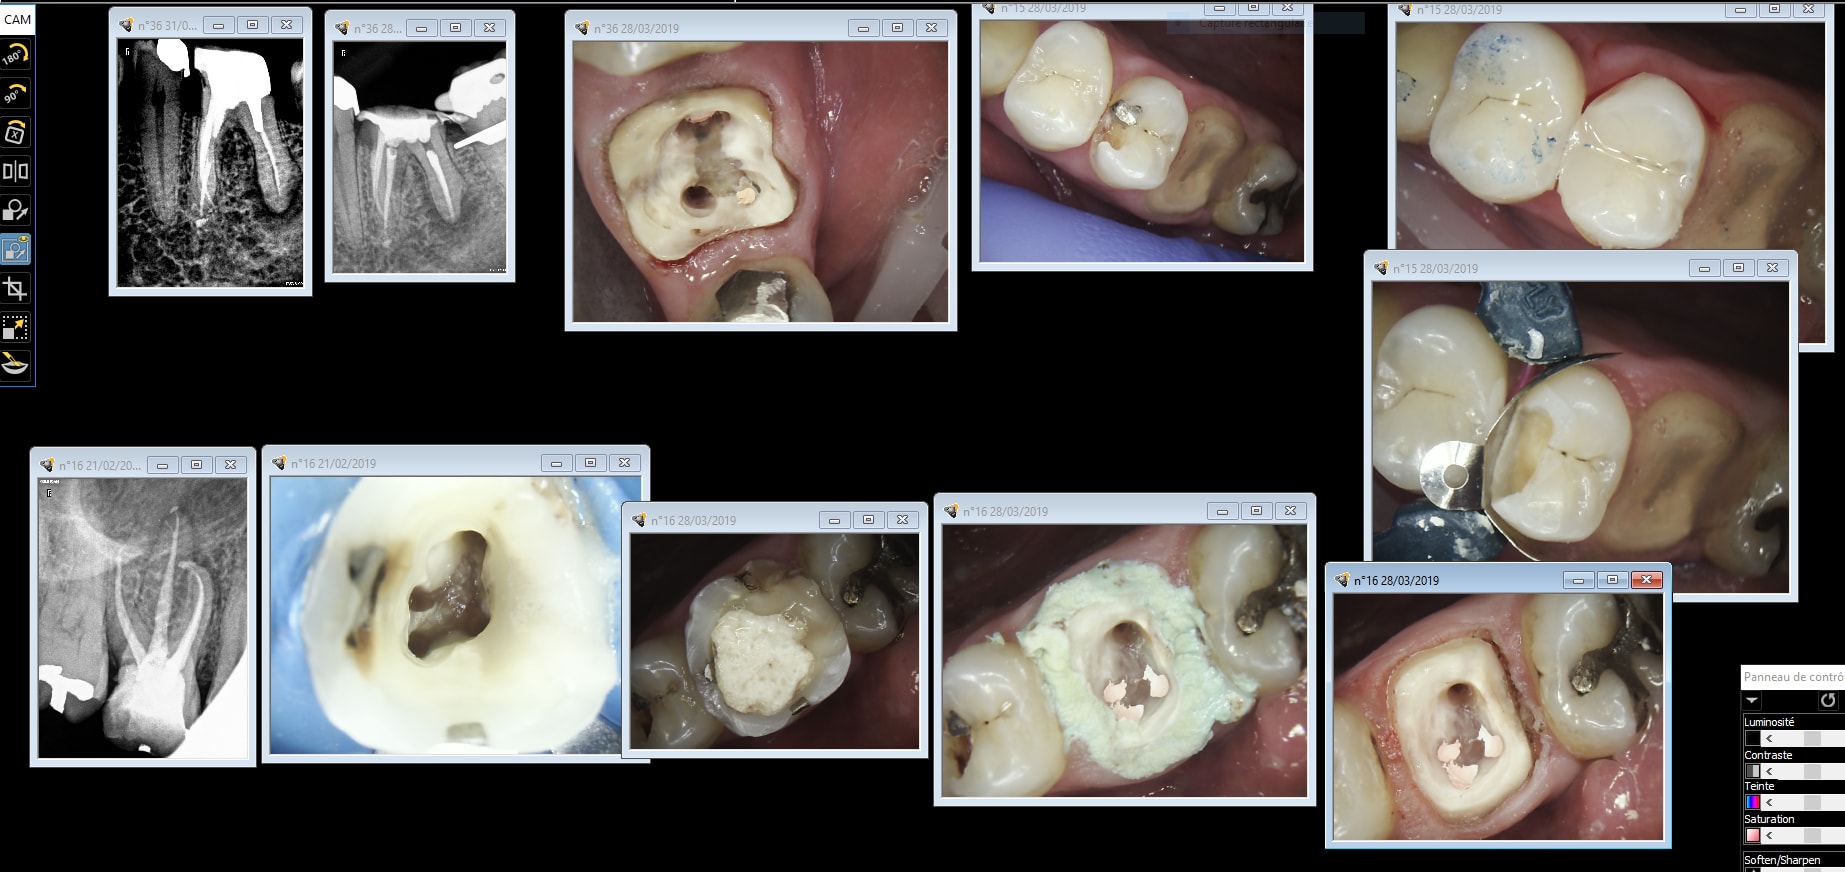

Idem que Chicot: Oneshot mais avec un peu plus d’éléments : 3IC, 8 CCM, 1 Stelitte. Aucune retouche autre qu’occlusale. Même Labo, c’est basique mais efficace

Amusant les dernières réactions. Et hallucinant à quel point certaines choses chocs. Pas l’impression d’avoir posté du « shit » sur ce forum et il serait bon d’arrêter de faire les jamais content, persécuté systématiquement, et ne pas non plus prendre tout à la lettre. Le One Shot, c’est l’empreinte et la RIM à partir d’une maquette et d’un travail en amont. Vous croyez au père noël ou quoi??? Ce que la caméra économise c’est empreinte secondaire, cire d’articulé et éventuellement biscuits si le couple wax-up/mock-up est aux p’tits oignons. Exploiter une caméra et les softs qui vont avec change énormément le rythme du travail mais ne nous autorise pas à se débrancher le cerveau.

Pas mal. Attachements + augmentation de DV en plus.